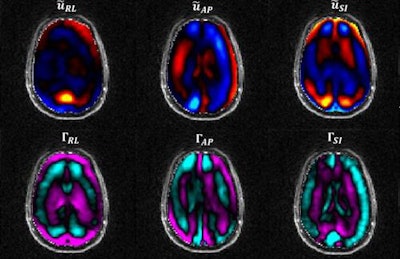

The goal of the study was to determine the extent to which these layers of membranes protect the brain, explained senior author Philip Bayly, PhD, chair of the university's mechanical engineering and materials science department, in a statement. To do so, the researchers used a vibrating pillow to introduce tiny skull vibrations and sensors embedded in a mouthguard to measure them during the MRE exams. They then measured brain motion using MRI, and compared the results in the volunteers with those in a gelatin model (J Biomech Eng, March 21, 2017).

The membrane layers in the six subjects significantly delayed and weakened the transfer of motion from the skull to the brain, compared with the gelatin model, the researchers found.